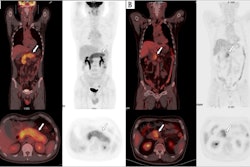

The researchers divided the cases into three groups: patients who had a PET/CT scan prior to the biopsy, those who had PET/CT following the biopsy, and those who did not undergo PET/CT. They then compared the accuracy of biopsies among the groups.

In total, 353 CT-guided lung biopsies were performed, with an overall diagnostic rate of 83.9 % (95.8 % malignant). The biopsy success rate was 88.8 % in the PET/CT prebiopsy group versus 78.9% in the group without PET/CT upfront, according to the findings.

Moreover, the biopsy success rate was 88.8 % when the biopsies targeted the PET/CT region showing the maximum tumor metabolic activity region, and only 52.8 % for biopsies that did not target these regions.

Finally, the researchers found that patients with a PET/CT prior to the biopsy underwent fewer needle passes (mean 2.6 vs. 3.1) required to obtain adequate sample sizes, they wrote.